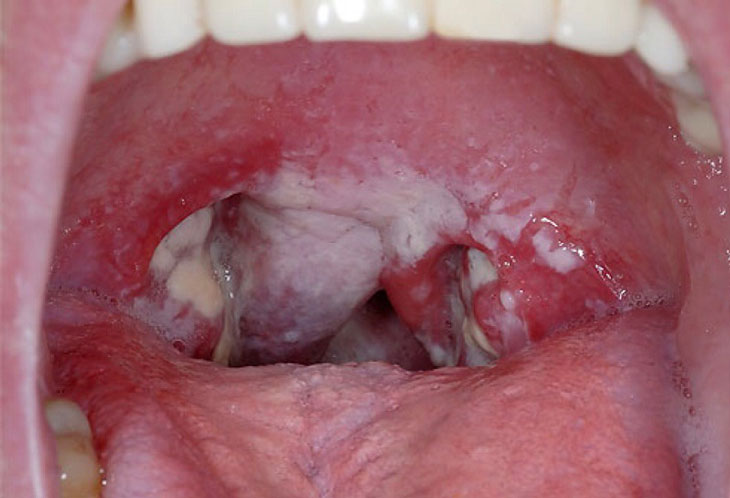

Triệu Chứng Ở Họng Và Mũi

- Đau họng, ho, sốt nhẹ và xuất hiện màng giả màu trắng hoặc xám trong họng.

- Có thể kèm theo khó nuốt, sưng amidan và hơi thở có mùi đặc trưng.

Khám Lâm Sàng

Quan sát triệu chứng, đặc biệt màng giả trong họng, sưng hạch và các dấu hiệu toàn thân. Bác sĩ đánh giá mức độ nhiễm trùng và nguy cơ biến chứng. Kết hợp với tiền sử tiêm chủng và tiếp xúc gần với bệnh nhân, khám lâm sàng giúp định hướng điều trị chính xác. Đồng thời, khám lâm sàng còn giúp theo dõi tiến triển của bệnh trong quá trình điều trị.